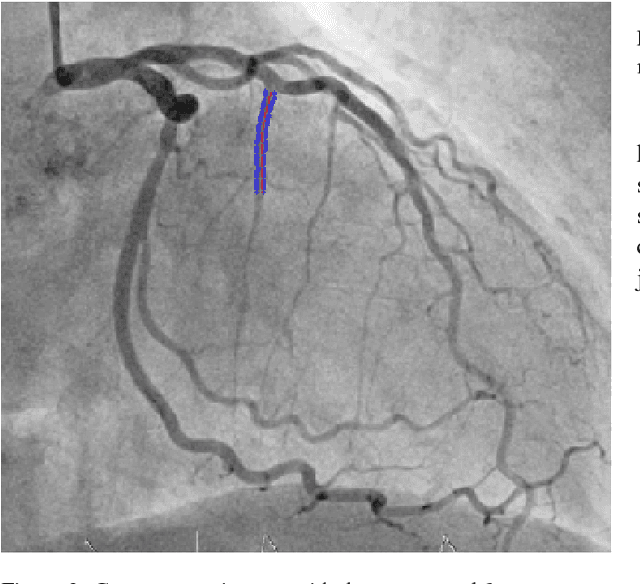

Abstract:The design and performance of computer vision algorithms are greatly influenced by the hardware on which they are implemented. CPUs, multi-core CPUs, FPGAs and GPUs have inspired new algorithms and enabled existing ideas to be realized. This is notably the case with GPUs, which has significantly changed the landscape of computer vision research through deep learning. As the end of Moores law approaches, researchers and hardware manufacturers are exploring alternative hardware computing paradigms. Quantum computers are a very promising alternative and offer polynomial or even exponential speed-ups over conventional computing for some problems. This paper presents a novel approach to image segmentation that uses new quantum computing hardware. Segmentation is formulated as a graph cut problem that can be mapped to the quantum approximation optimization algorithm (QAOA). This algorithm can be implemented on current and near-term quantum computers. Encouraging results are presented on artificial and medical imaging data. This represents an important, practical step towards leveraging quantum computers for computer vision.